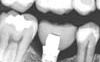

Image 03

Xray on completed inlay showing excellent fit in the deep area.